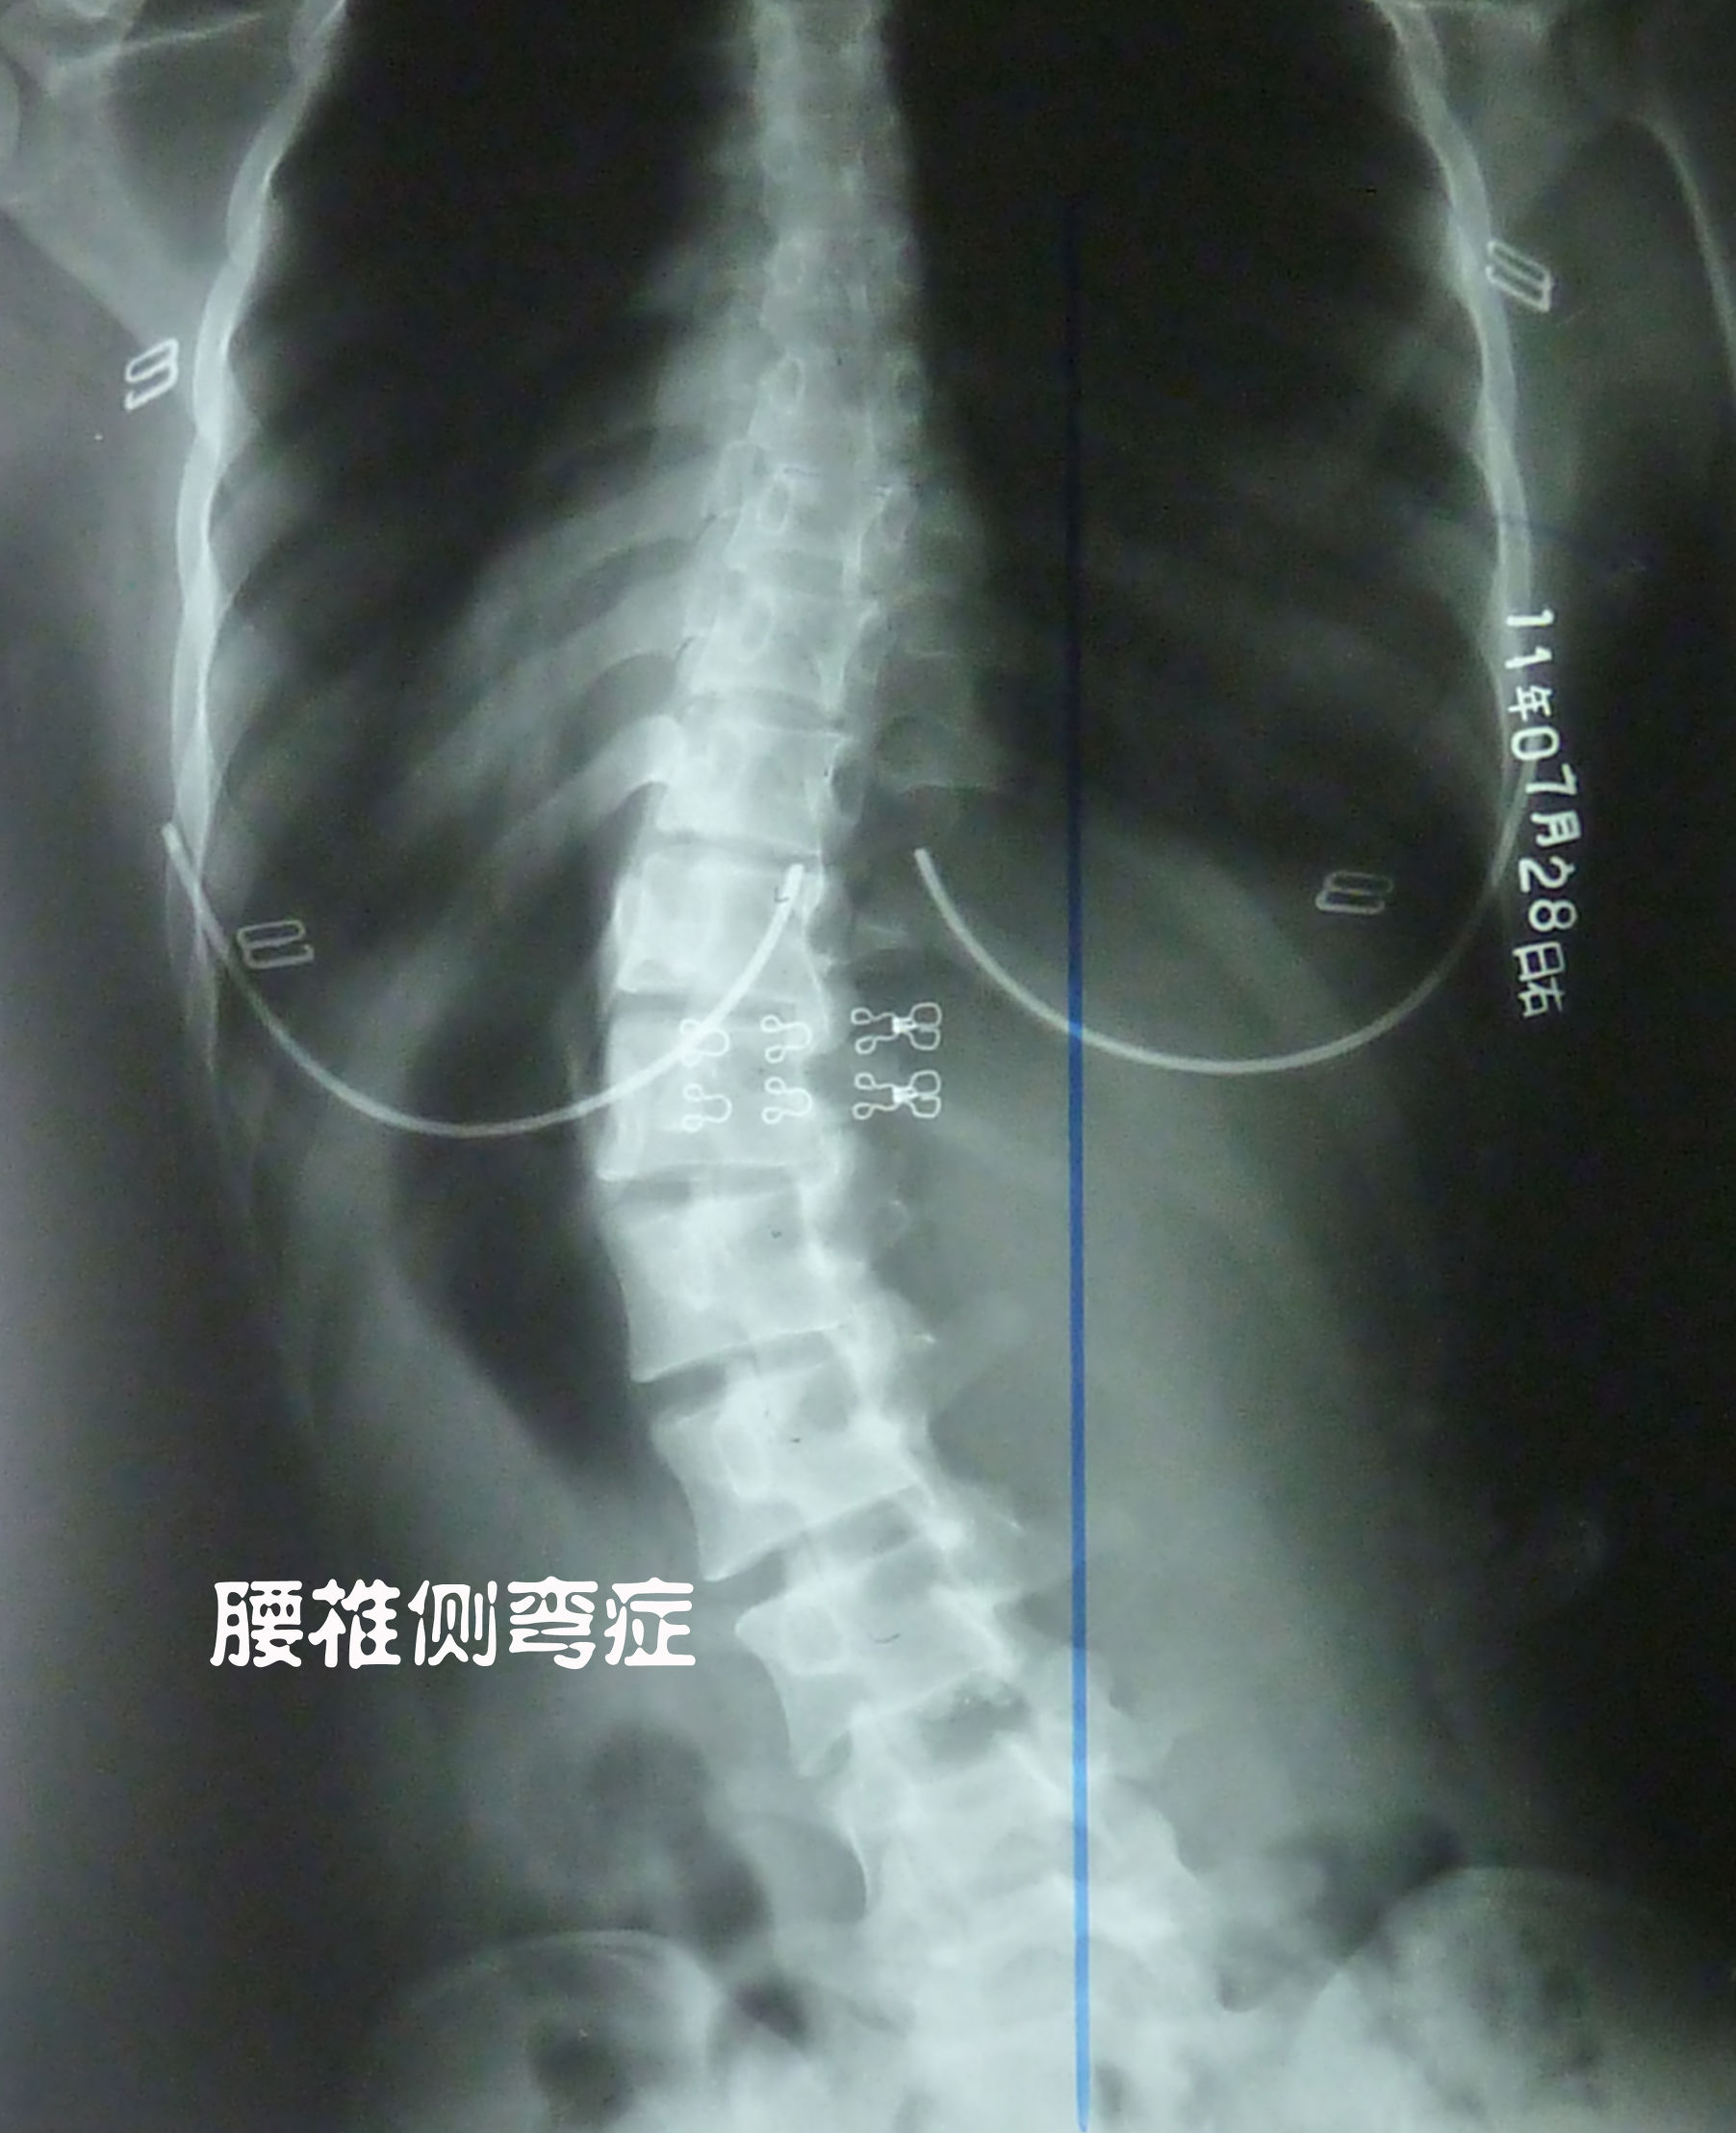

如下图所示:腰椎侧弯的人,一般都伴随腰椎间盘突出。